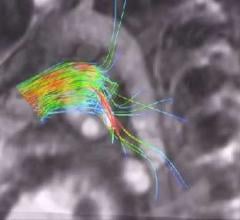

Despite decades of progress in breast imaging, one challenge continues to test even the most skilled radiologists ...